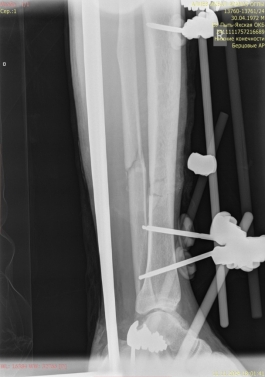

Ввиду выраженного отечного синдрома в области перелома была выбрана методика конверсионного остеосинтеза. На первом этапе были выполнены открытая репозиция, остеосинтез наружной лодыжки пластиной, фиксация голеностопного сустава аппаратом внешней фиксации (рис. 2).

Рис. 2.